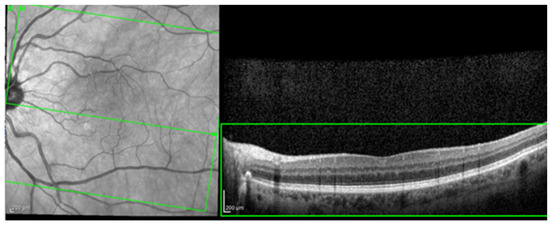

The most common image artifacts observed were distortions and image noise. All images were included in the analysis, without having any external image adjustments or quality enhancers, in order to emulate “real world” everyday clinical practice conditions (see Figure 2 and Figure 3).

Figure 3.

Image noise. Observe the snow-like appearance of the scan (green box). This artifact appears when the medium through which the infrared beams pass are not perfectly transparent (example: cataracts), making it very difficult to interpret the image.